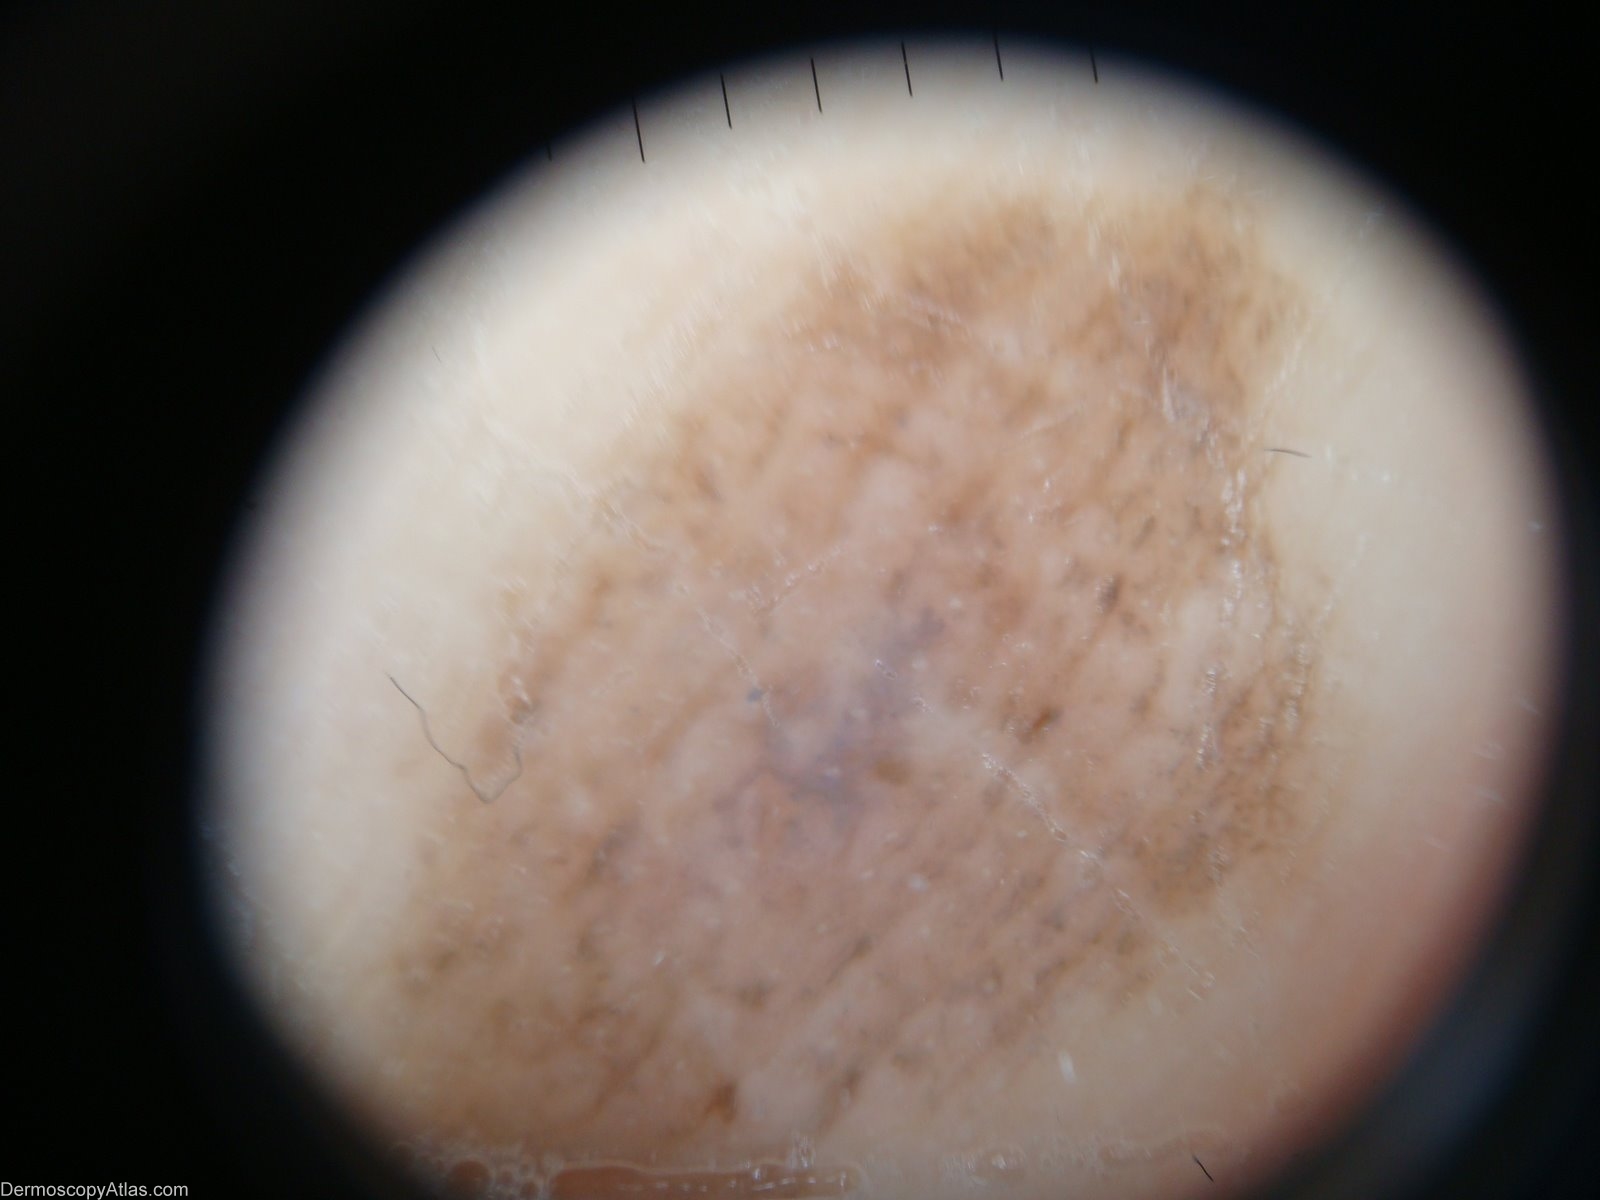

Diagnosis - Acral congenital naevus

Diagnosis: Acral congenital naevus